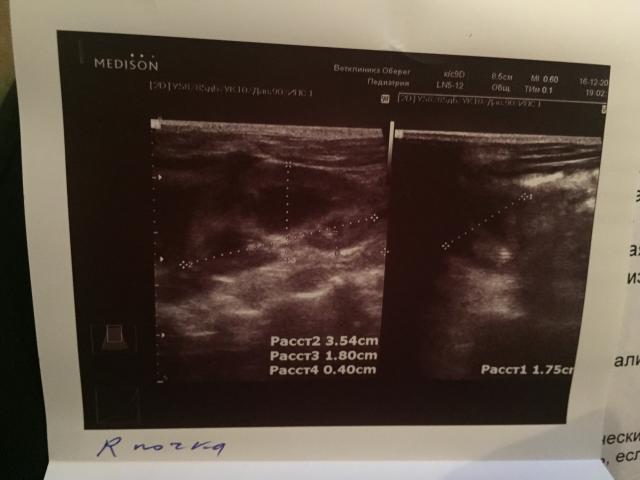

Если можно, то немного подробнее. На основании чего вам поставили такой диагноз, только на основании проведенного УЗИ? Может быть, собаке брали какие-то анализы? Если да, то выложите, пожалуйста, здесь их результаты. Если только данные УЗИ, то это разговор ни о чем (я имею ввиду панкреатит). Гастрит по данным УЗИ вообще не ставят.

К сожалению, ничего не могу рассмотреть. Попробуйте сами прочесть описание с фото. Если сможете, сделайте снимок более качественным. Или можно снять крупнее по частям. Может быть, тогда буквы будут видны более четко.

Спасибо, фотографии четкие. Я все прочитал. Как я и думал, там и "не пахнет" никаким гастродуоденитом, а тем более, панкреатитом.